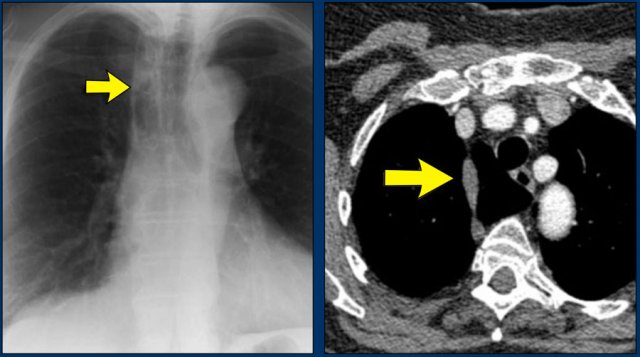

Hidden area (5): Mass Behind the First Rib

In some patients, an accessory joint at the anterior aspect of the first rib may simulate a mass, as we learned earlier.

However this area is also a "hidden zone", where true lesions can be masked.

• In this case, a small lung carcinoma was obscured by the left first rib on the PA view.

• On the lateral film, the lesion is visible in the retrosternal space.

Continue with the PET-CT...

Subsequent PET-CT imaging confirmed a hypermetabolic tumor (arrow), with metastases to the bone and liver.

• Diagnosis was confirmed via biopsy of an osteolytic metastasis in the iliac bone.